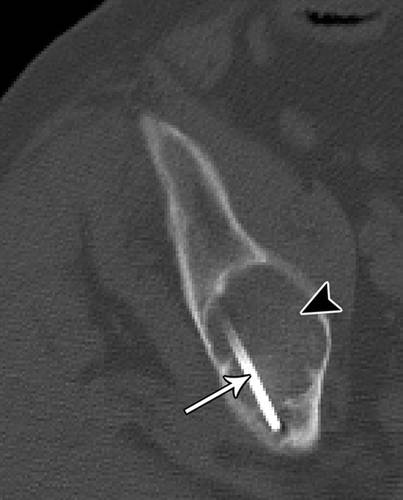

7 - 74岁男性成骨细胞性骨肉瘤穿刺。

![]()